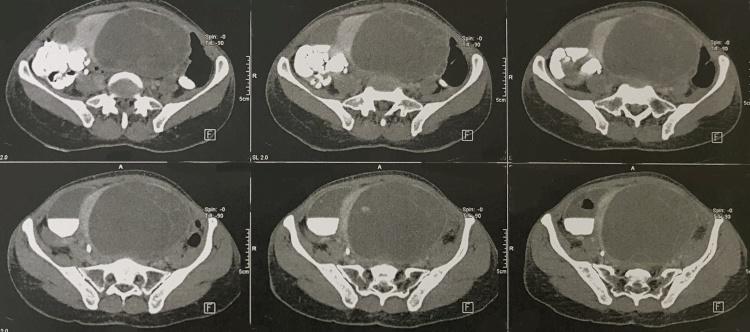

PRESENTATION OF CASE

We here report a case of primary uterus hydatid cyst that we had to remove her uterine on left ovary and fallopian tube. Generalized toxic shock and infection due to cyst rupture or organ dysfunction due to invasion (like our patient) or pressure of cyst are complications of this cyst.

Because of low incidence of hydatid cysts in uterus it can be misdiagnosed by mimicking other conditions such as multi-cystic ovarian tumor, hemorrhagic ovarian cyst, endometrioma, cystadenoma, leiomyoma and etc.

病例介绍

我们在此报告一例原发性子宫包虫囊肿病例,我们不得不切除其左侧卵巢和输卵管的子宫。囊肿破裂导致的全身性中毒性休克和感染,或因囊肿侵袭(如我们的患者)或压迫导致的器官功能障碍,是这种囊肿的并发症。

由于子宫包虫囊肿发病率低,它可能会被误诊为其他病症,如多囊卵巢肿瘤、出血性卵巢囊肿、子宫内膜瘤、囊腺瘤、平滑肌瘤等。